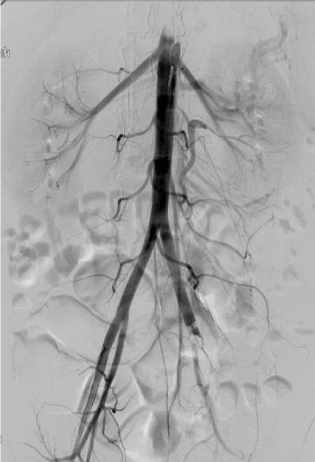

This revealed occlusive lesions in both lower extremities. On the left side, total occlusion of the left common iliac at its site of bifurcation to internal and external iliac arteries was noted with no distal filling beyond the occlusion (Figure 1). On the right side, there was occlusion of the proximal profunda femoris artery (PFA) and at the distal popliteal, there was a hazy filling defect with brisk filling of anterior tibial artery via collaterals but poor filling of peroneal and posterior tibial.

Figure 1. Left leg: Occluded left common iliac artery due to septic embolism with no distal flow